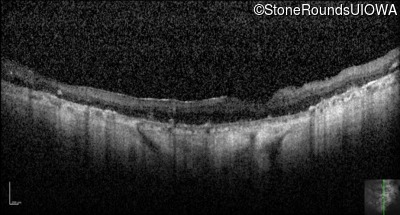

Optical Coherence Tomography - Right - Hand Motion sc

Exemplar / OCT Stack